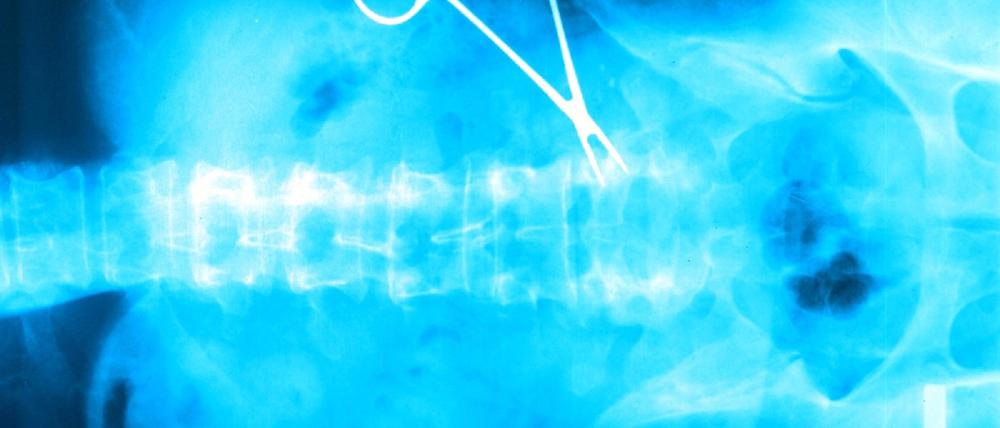

Medizin: Ärztepfusch bei jeder zehnten Behandlung

Jede zehnte medizinische Behandlung in der Europäischen Union ist nach Angaben der EU-Kommission fehlerhaft. Die Bundesverbraucherzentrale fordert als Reaktion darauf ein "Patientenrechtegesetz" und die Beweislastumkehr für Behandlungsfehler.

In Deutschland landen laut "Welt" rund 10.000 Fälle jährlich vor Gericht oder bei den medizinischen Diensten der Krankenversicherer, weil Patienten sich falsch behandelt fühlen. Insgesamt würden rund 40.000 Fälle pro Jahr bekannt, in denen sich Patienten falsch behandelt fühlen - die Dunkelziffer liege nach Angaben von Experten aber deutlich höher. Am häufigsten werden laut Bundesärztekammer Chirurgen Fehler vorgeworfen. Es folgen Orthopäden, Internisten und Gynäkologen. In der EU treten laut Kommission pro Jahr allein in Krankenhäusern bei medizinischen Behandlungen in 15 Millionen Fällen Fehler auf. (jar/jr/dpa/AFP)